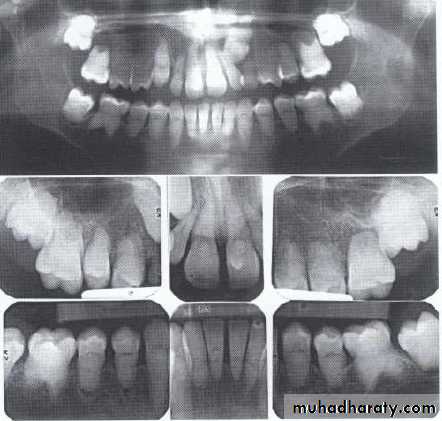

Dentin dysplasia, type I. panoramic & periapical films of the same case show the short and poorly developed roots, obliterated pulp chambers and root canals, and periapical inflammatory lesions.

Radiographically:

Deciduous teeth:

roots are extremely short

pulps almost completely obliterated

Permanent teeth:

abnormally large pulp chambers in coronal portion of tooth.

Type II (Coronal Type)

Dentin dysplasia, type II. panoramic &periapical films of the same case show obliteration of the pulp chamber, reduction in the caliber of root canals, and pulp stones obscuring the flame-shaped pulp chambers.

Periapical inflammatory lesions are associated with some of the mandibular anterior teeth.